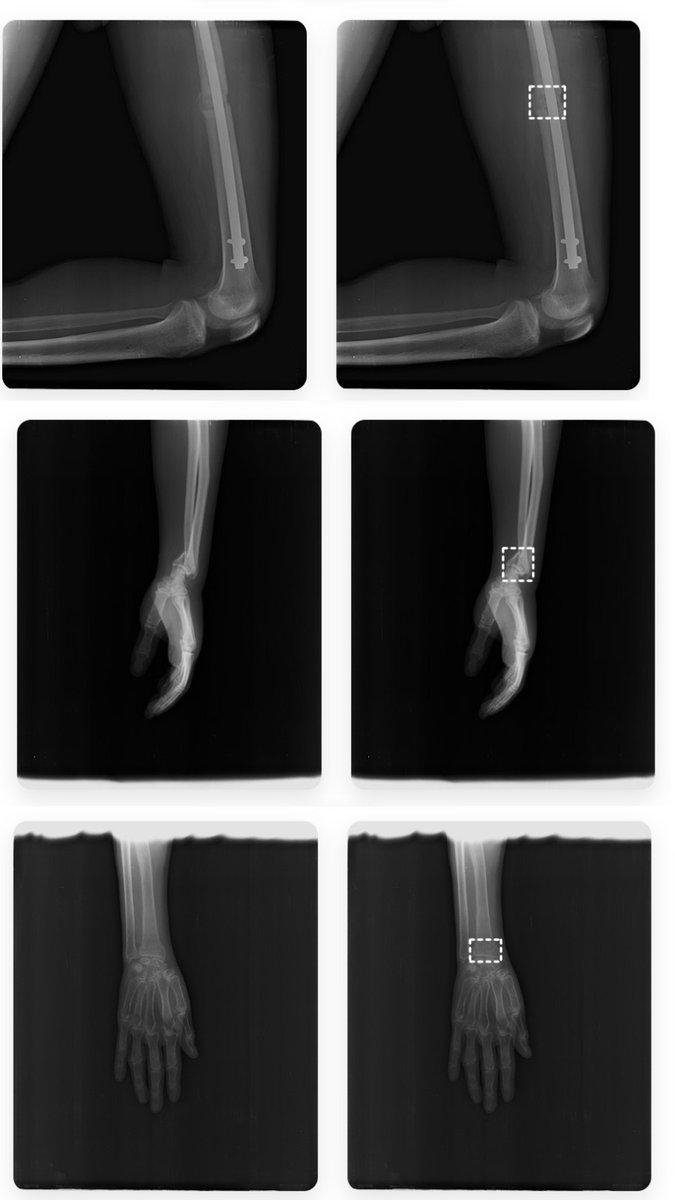

At Easiofy, three women engineers built ImagiXAI to speed cancer planning and bring advanced imaging to remote India.